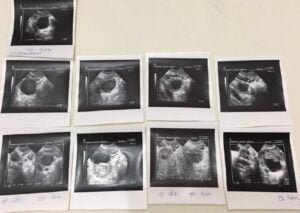

Aqui são as imagens dos cistos ovarianos endometrióticos antes das sessões de acupuntura:

A paciente do sexo feminino foi diagnosticada com endometriose em ambos os ovários. Nos exames feitos antes do tratamento foram visíveis cistos de “chocolate” em ambos os ovários. Desde o diagnóstico, a paciente estava em uso de terapia hormonal (há um ano e um mês). Antes de iniciar o tratamento com acupuntura a terapia hormonal foi interrompida. O ciclo menstrual é regular, porém muito doloroso. A paciente também sofria de acne hormonal no rosto.

O paciente masculino fez 4 sessões para melhorar a qualidade do esperma. A paciente do sexo feminino tinha cistos ovarianos que desapareceram após 7 sessões e conseguiu engravidar.